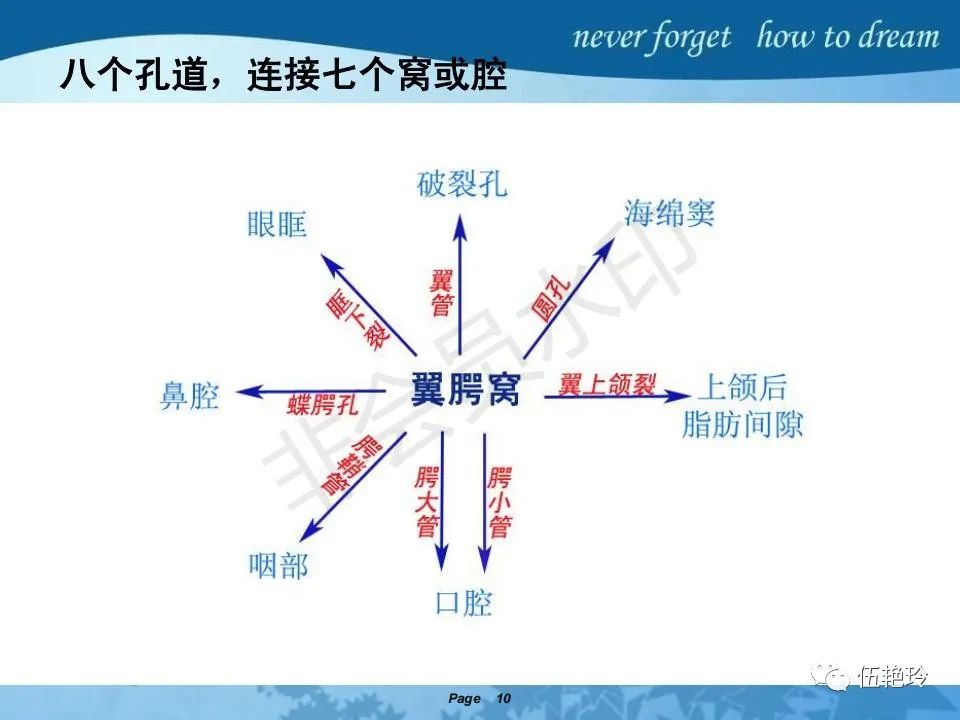

翼腭窝的解剖结构与鼻咽癌侵犯

2.31 向上颅内:①鼻咽顶壁→破裂孔(岩尖、斜坡)→蝶窦、海绵窦;②鼻咽顶壁→蝶骨基底部→蝶窦、海绵窦;③鼻咽侧壁→茎突前间隙→蝶骨大翼(卵圆孔)→海绵窦;④鼻咽侧壁→茎突前间隙→翼腭窝→ 颞下窝;⑤鼻咽前壁→鼻腔→翼突、翼腭窝→眶下裂→眶尖→海绵窦;⑥鼻咽前壁→鼻腔→上颌窦、筛窦;